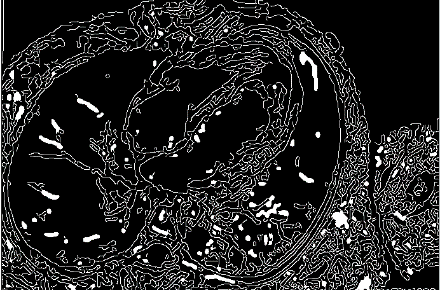

3. Proposed Unit-Modified SwinTransformer Network

UMSN is a different approach that engages a unique master plan by associating the similar-dimension pixels into segments ranging from 2×2 to 16×16. This segmentation perspective is instrumental in enhancing the accuracy of disease detection. Within this grouped pixel analysis, an indispensable layer is trained using pixels that manifest unanimous feature extraction. This training methodology allows the framework to determine the segment boundaries efficaciously. During the boundary detection procedure, this process organizes the coinciding pixel boundaries with similar features for training the fundamental segment of consecutive boundaries. The UMSN denotes an innovative advancement in cardiac MRI observation for disease detection and diagnosis. By associating the pixels, determining the disparities, and purifying its training process, UMSN contributes importantly to the prior detection of cardiac diseases, which leads to better patient care and results in the realm of smart health. In Figure. 1 the overall process of the proposed network is portrayed.

Figure 1. Overall process of the proposed network